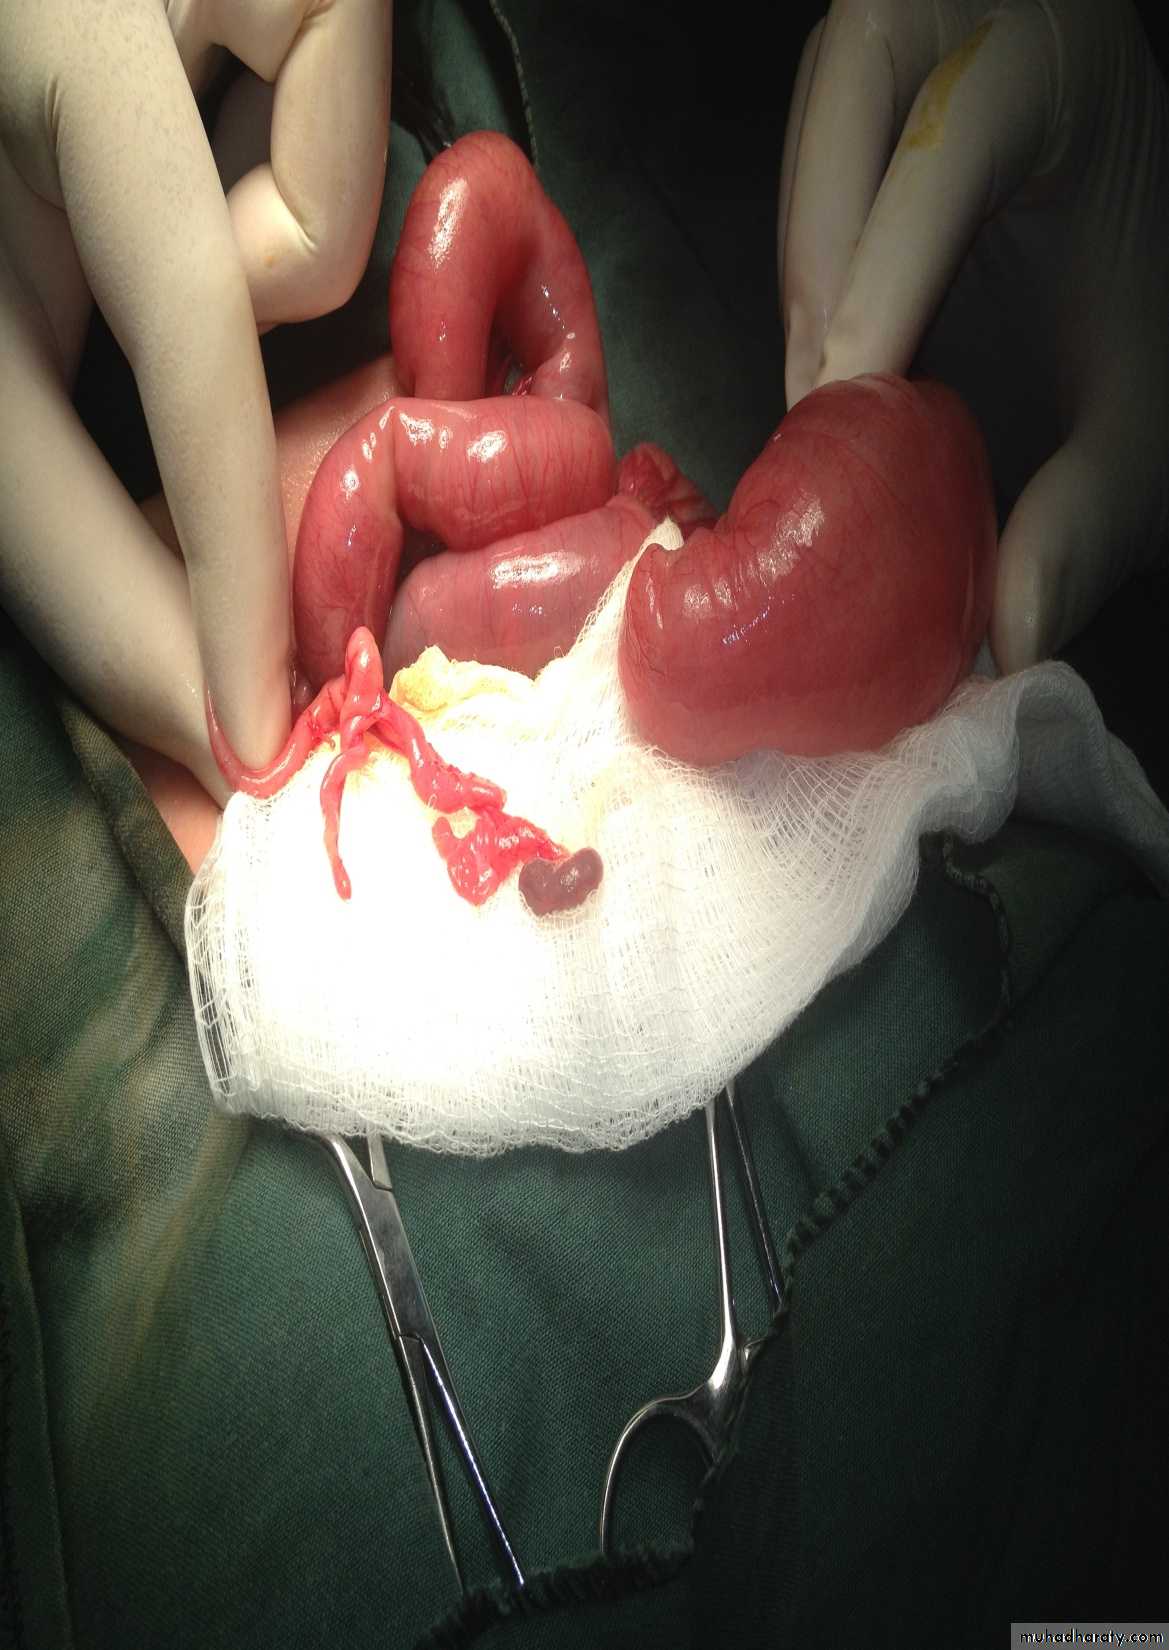

Abdominal Wall Defects

Tutorial